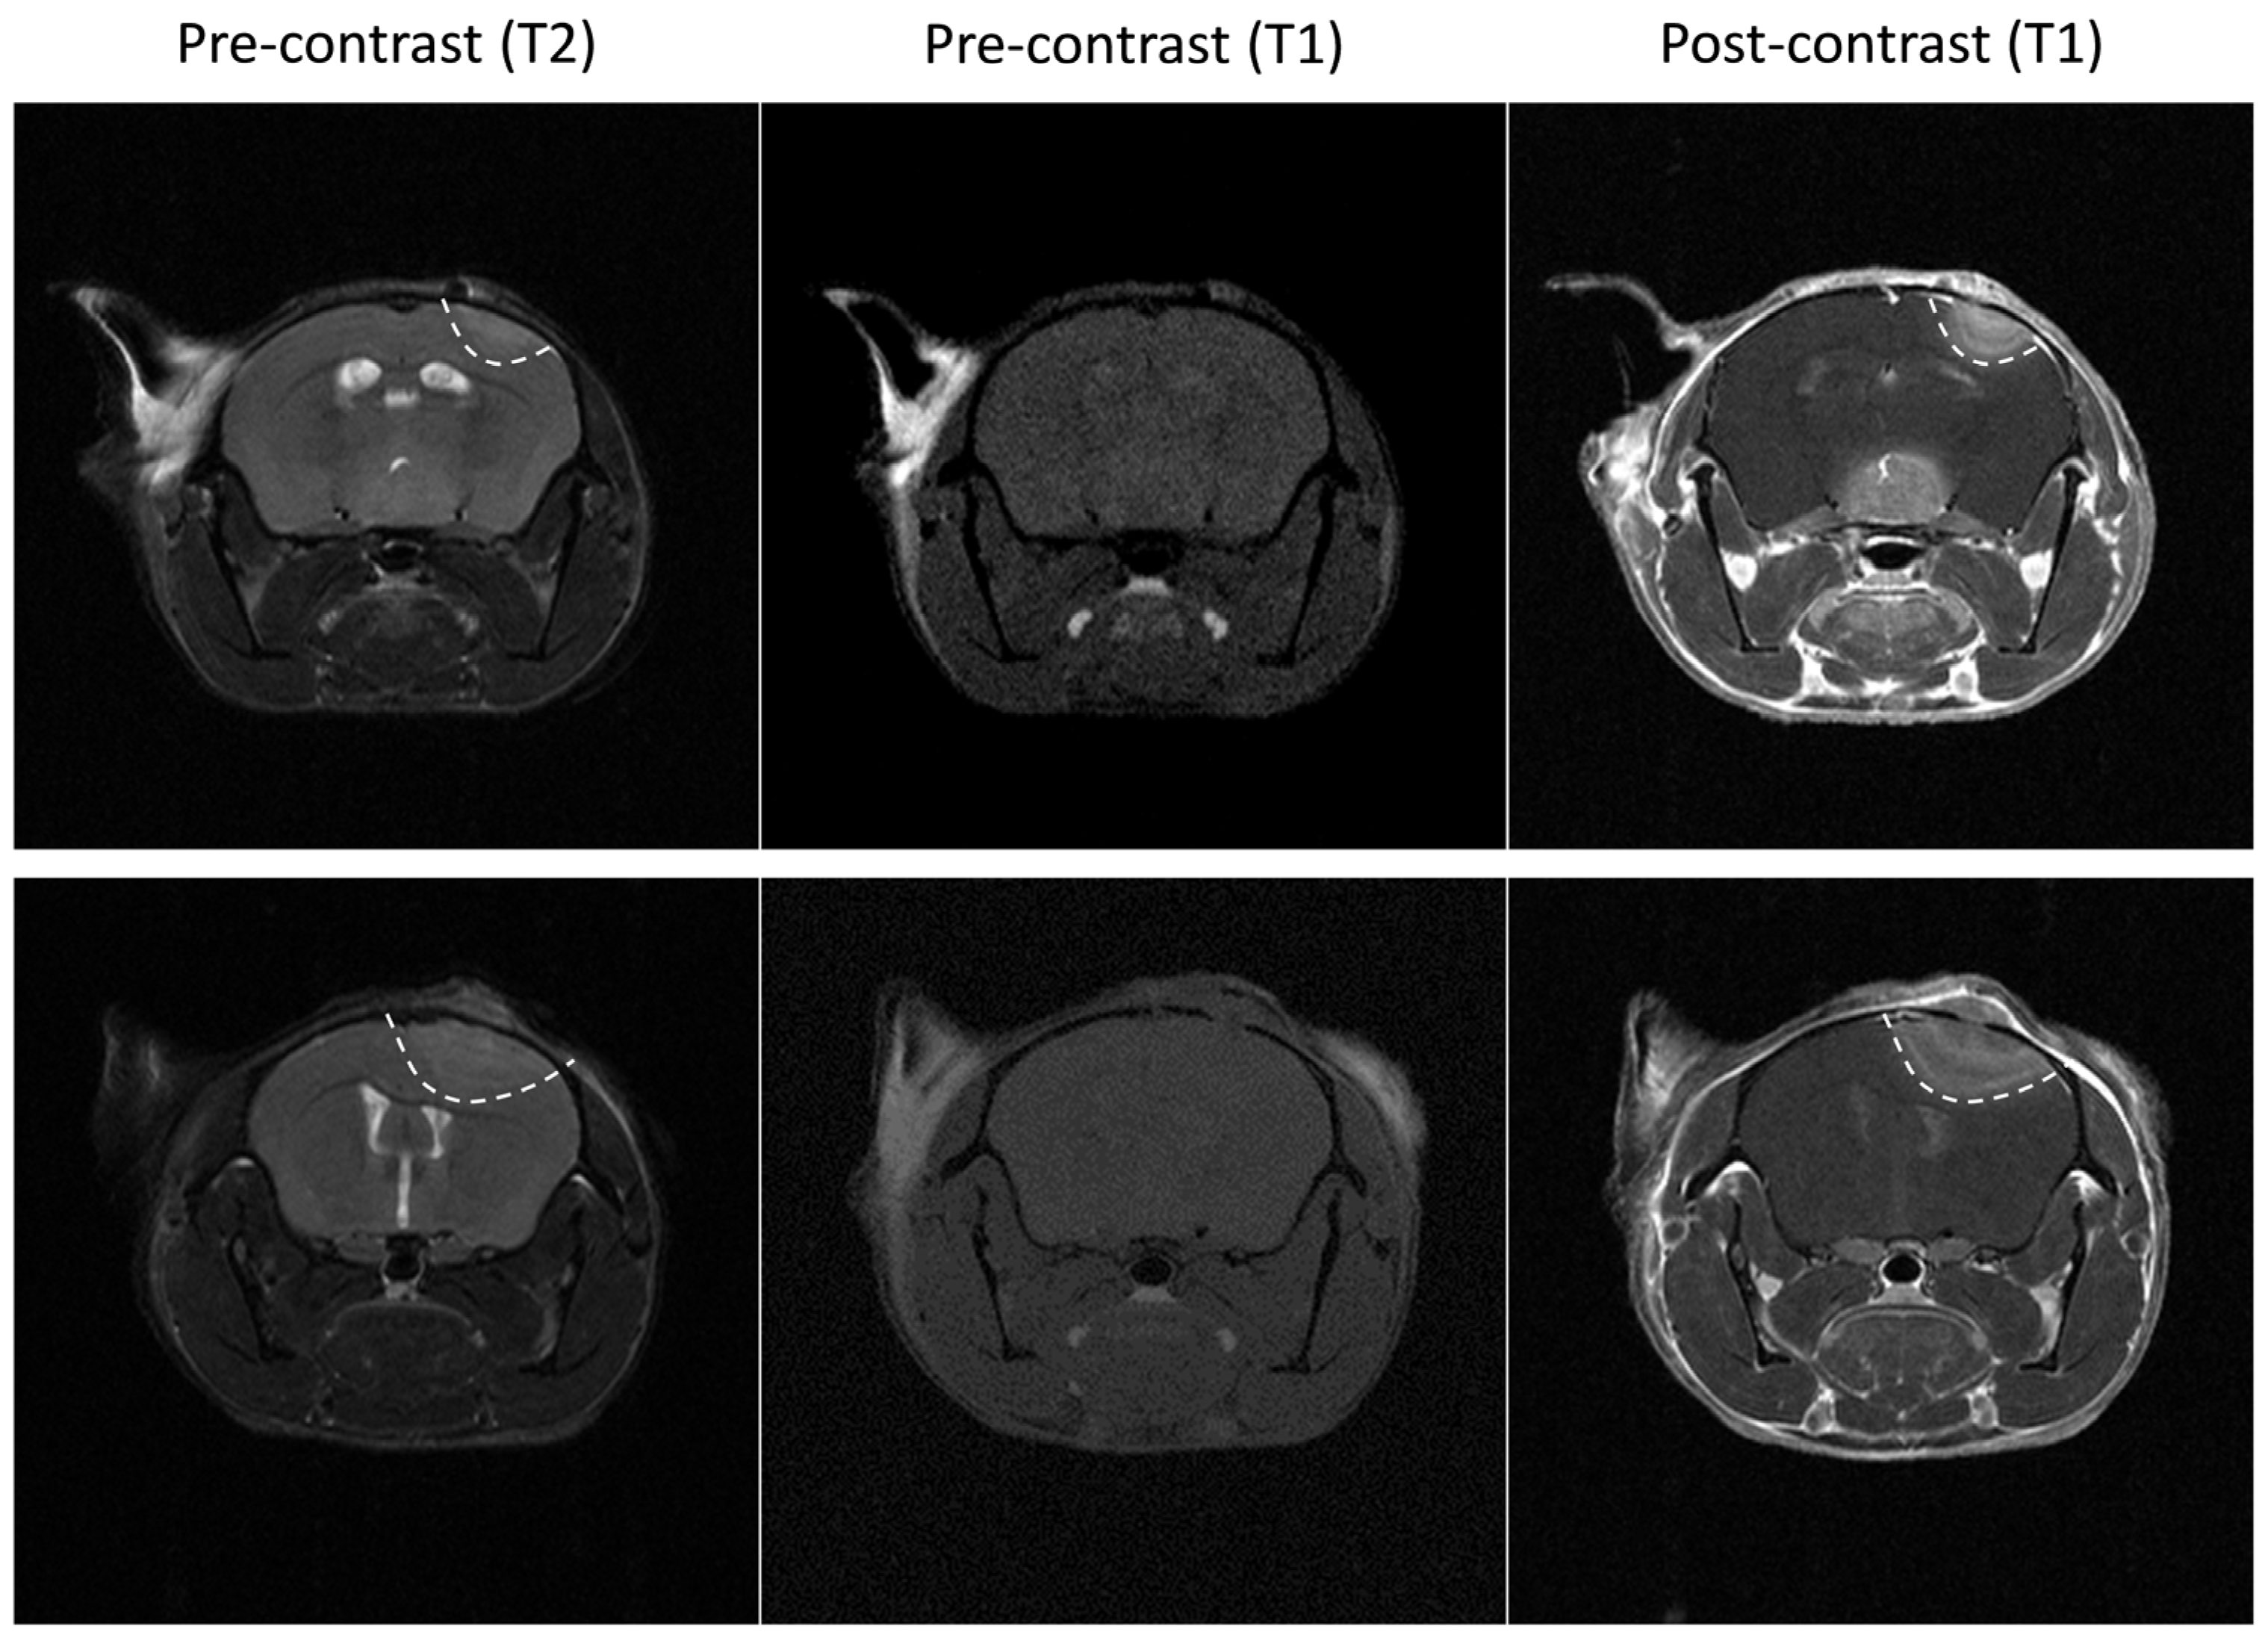

2.3. Tumor Imaging

2.3.2. Magnetic Resonance Imaging